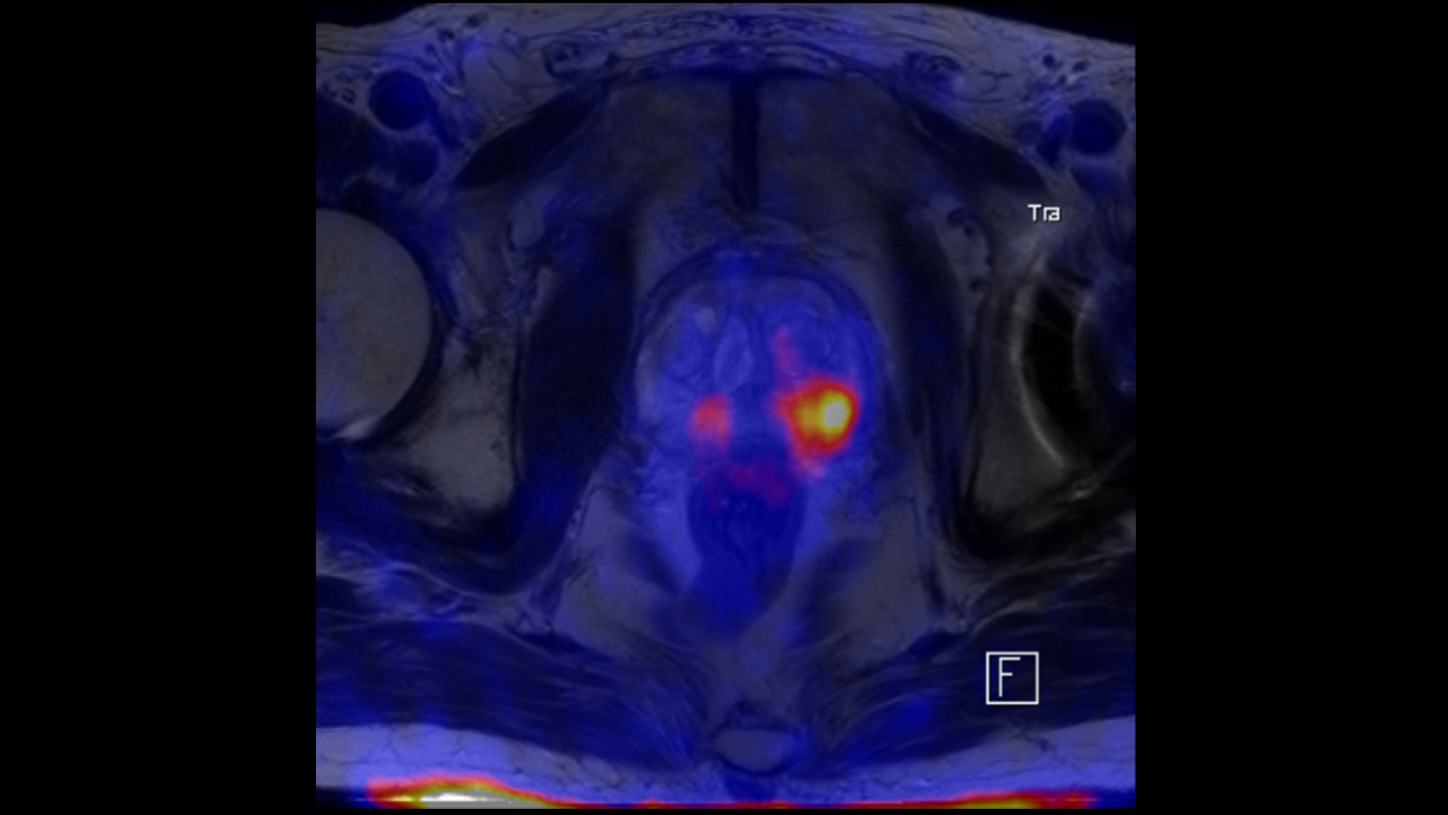

BIOGRAPH One is designed to support one patient-centric pathway to personalized care. By seamlessly integrating PET and MR into one comprehensive exam, it will support clinicians from diagnosis and staging, through a personalized therapy decision to regular therapy assessments to excel precision and support one streamlined approach.

BIOGRAPH One is designed to excel in PET/MR precision to support confident diagnostic decisions. Featuring the Optiso UDR Pro detector with the largest 35 cm axial FOV2 in PET/MR, it is designed to enable comprehensive capture with excellent sensitivity and ultra-fast TOF3 in real time – delivering clear, detailed images.